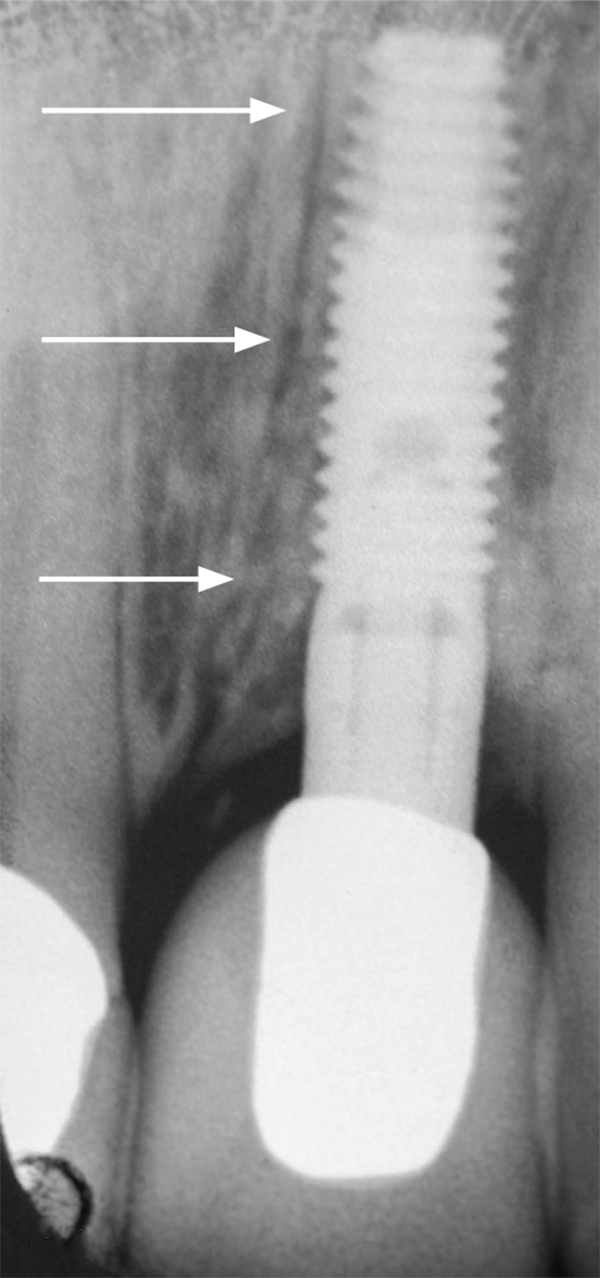

Fig 1. A periapical radiograph of an implant placed in the left central incisor position. The implant has an angulation toward the distal (arrows) to avoid penetration of the nasopalatine canal.

Fig 4. A cross-sectional view of a CBCT scan depicting the disparity between the height of the labial and palatal bony margins of the nasopalatine canal. In this instance, there was a 7-mm height discrepancy between the bony margins.

Figure 4